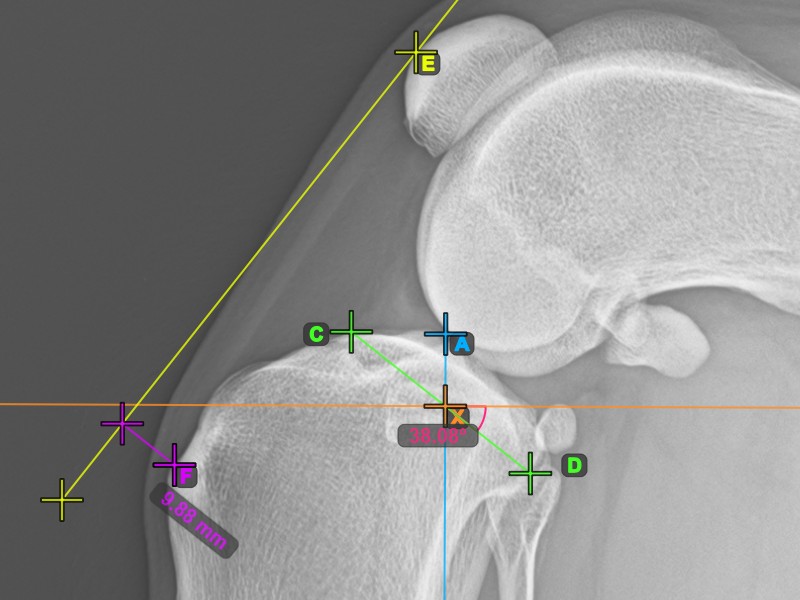

To complete the TTA measurement procedure mark the most dorsal point of the Crista Tibiae (Tuberositas Tibiae). The distance between the Tuberositas Tibiae and the line passing along the most cranial point of the Patella is the required adjustment for the TTA procedure.

The image below depicts the usual placement of the tibial tuberosity, the most prominent point of the tibial crest.